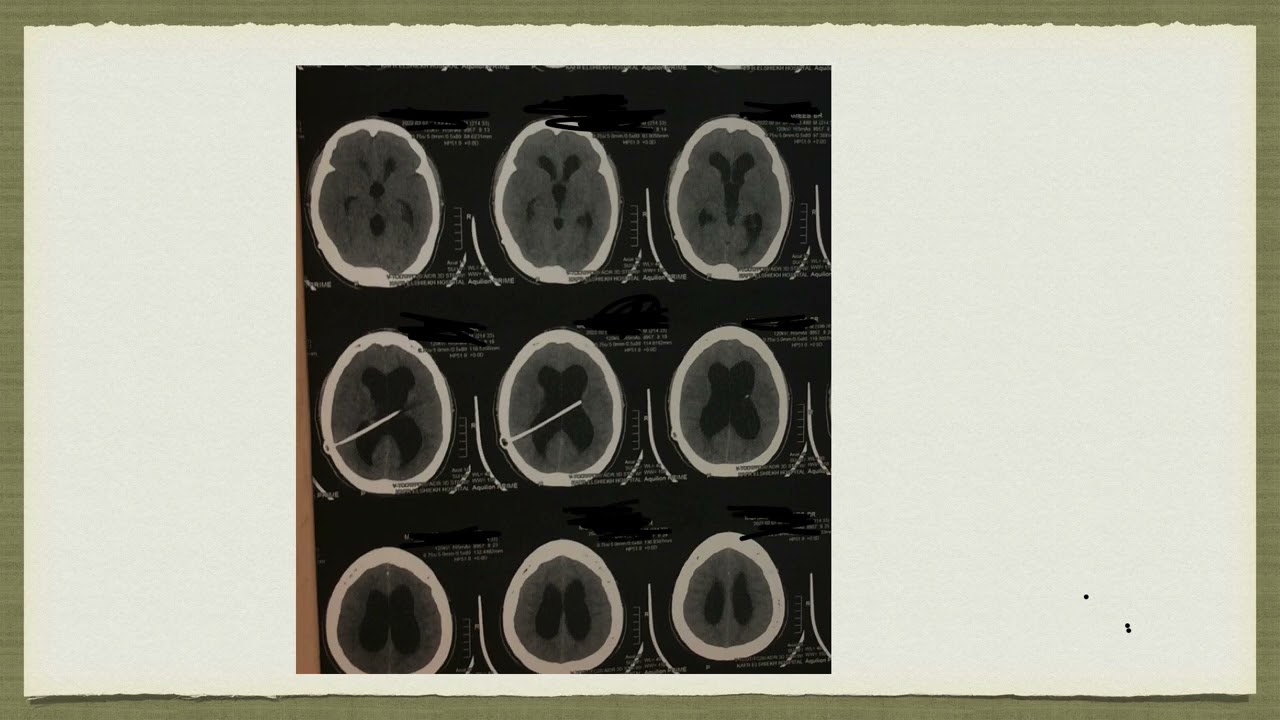

صورة غير معتادة من انسداد صمام المخ : تكون كيس كبير في النخاع الشوكي و ضعف بالاطراف

صورة غير معتادة من انسداد صمام المخ : تكون كيس كبير في النخاع الشوكي و ضعف بالاطراف...و تم إزالة الصمام نهائيا و عمل جراحة كي الحنفية المعدلة